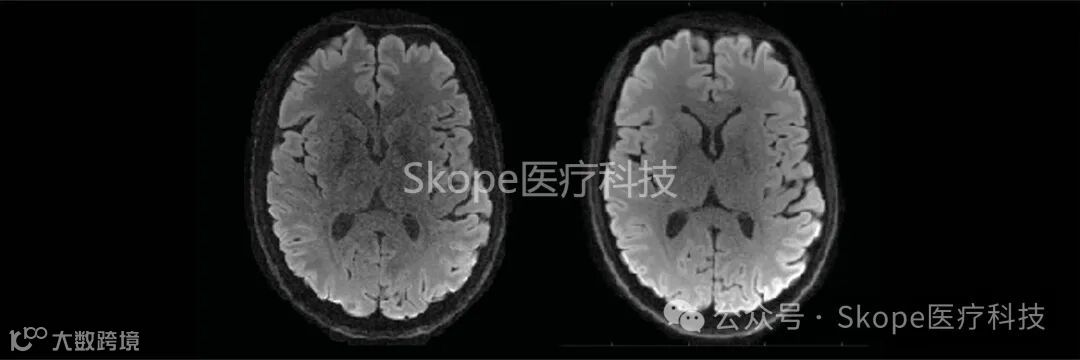

实际上,由强扩散梯度引起的涡流电流是扩散加权成像领域中图像伪影的最重要来源。可以使用涡流电流抵消策略来减轻这些效应,但代价是较长的回波时间和较低的信噪比。通过监测读数轨迹,您可以放弃这些补偿方法并简化采集过程。在下面所示的示例中,将一个EPI和一个带有单个重调谐RF脉冲的螺旋扩散加权采集进行了比较。螺旋读数的较短回波时间(TE)直接转化为更高的信噪比,这可以用来换取更高的空间分辨率。

Further reading: Lee et al. (2020), ETH Zurich. On the signal‐to‐noise ratio benefit of spiral acquisition in diffusion MRI.

*使用skope-i重建的高分辨率EPI(TE=71毫秒)(左)和螺旋(TE=42毫秒)(右)平均DWI图像 (来源:Skope)

Courtesy Yoo Jin Lee, IBT ETH Zurich and University of Zurich.